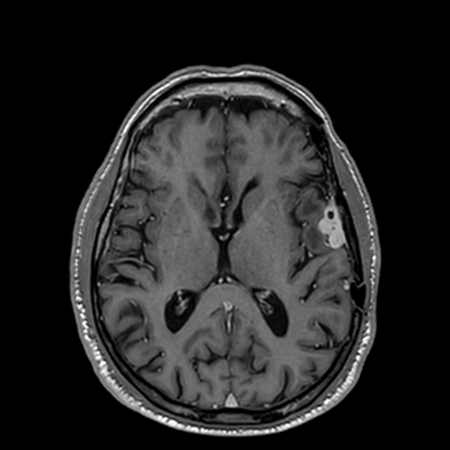

See the Difference

Compare the visual quality of our AI-enhanced images against traditional full-dose scans

AI-Enhanced

DeepGAD™ synthesized